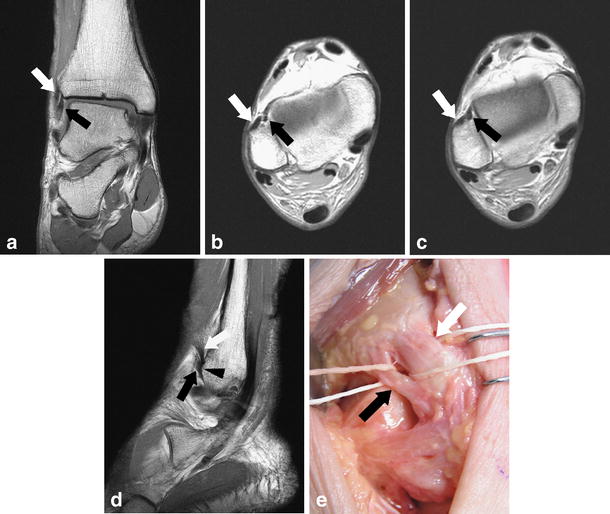

MRI appearance of surgically proven abnormal accessory anterior What Is Bassett S Ligament 17 now, also known as bassett’s ligament, it lies inferior and parallel to the aitfl. the anterior inferior tibiofibular ligament (aitfl) is part of the lateral collateral ligament complex of the ankle. bassett’s ligament, a thickened distal fascicle of the anterior inferior tibiofibular ligament (aitfl) that extends. the inferior fascicle of the aitfl was identified as a. What Is Bassett S Ligament.